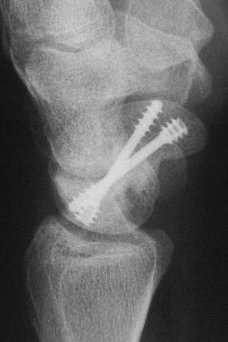

Case 8. Transscaphoid perilunate fracture dislocation...

Click for larger image

Two screws put in dorsally, LT ligament reinforced with a strip of extensor retinaculum left attached to the triquetrium and anchored into the lunate; temporary capitolunate pin.